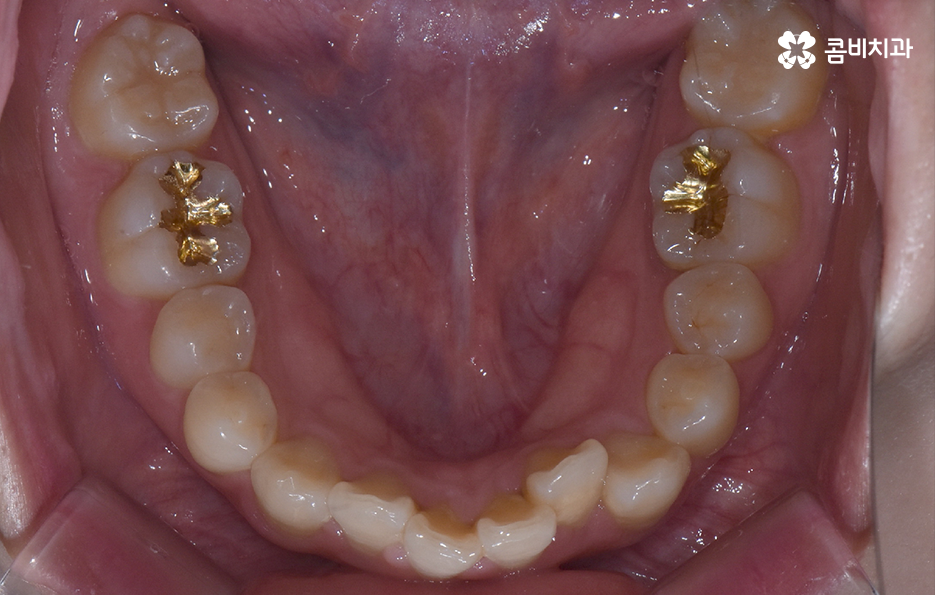

오늘 덧니 비발치 교정 사례로 보시는 환자분의 경우에는 윗니와 아랫니 앞니 부분에 조금씩 덧니가 있는 상태로 덧니를 제외하면 대체적으로 치열 상태는 고른 편이며 덧니 교정 사례 중에서는 돌출입도 함께 개선해야 하는 경우가 많지만 위 환자분의 경우에는 돌출입의 정도가 양호했고 입술라인 역시도 정상 범위에 가까웠기 때문에 발치를 필요로 하지 않았지만 치아의 이동 공간과 보다 자연스러운 입술라인 그리고 얼굴형과의 조화를 고려하여 악궁 확장과 어금니 후방 이동을 적절히 활용하여 교정 치료가 진행되었다고 볼 수 있어요

대부분의 발치 교정의 경우 작은 어금니를 발치하여 치아의 이동 공간을 확보하는 경우가 많다면 덧니 비발치 교정의 경우 발치교정 만큼은 아니더라도 치아를 이동 시킬 공간을 약간이라도 확보해야 하기 때문에 악궁 확장이나 치간삭제를 하는 경우가 있으며 어금니 후방 이동이 필요할 경우에는 사랑니 발치를 해야할 수 있어요